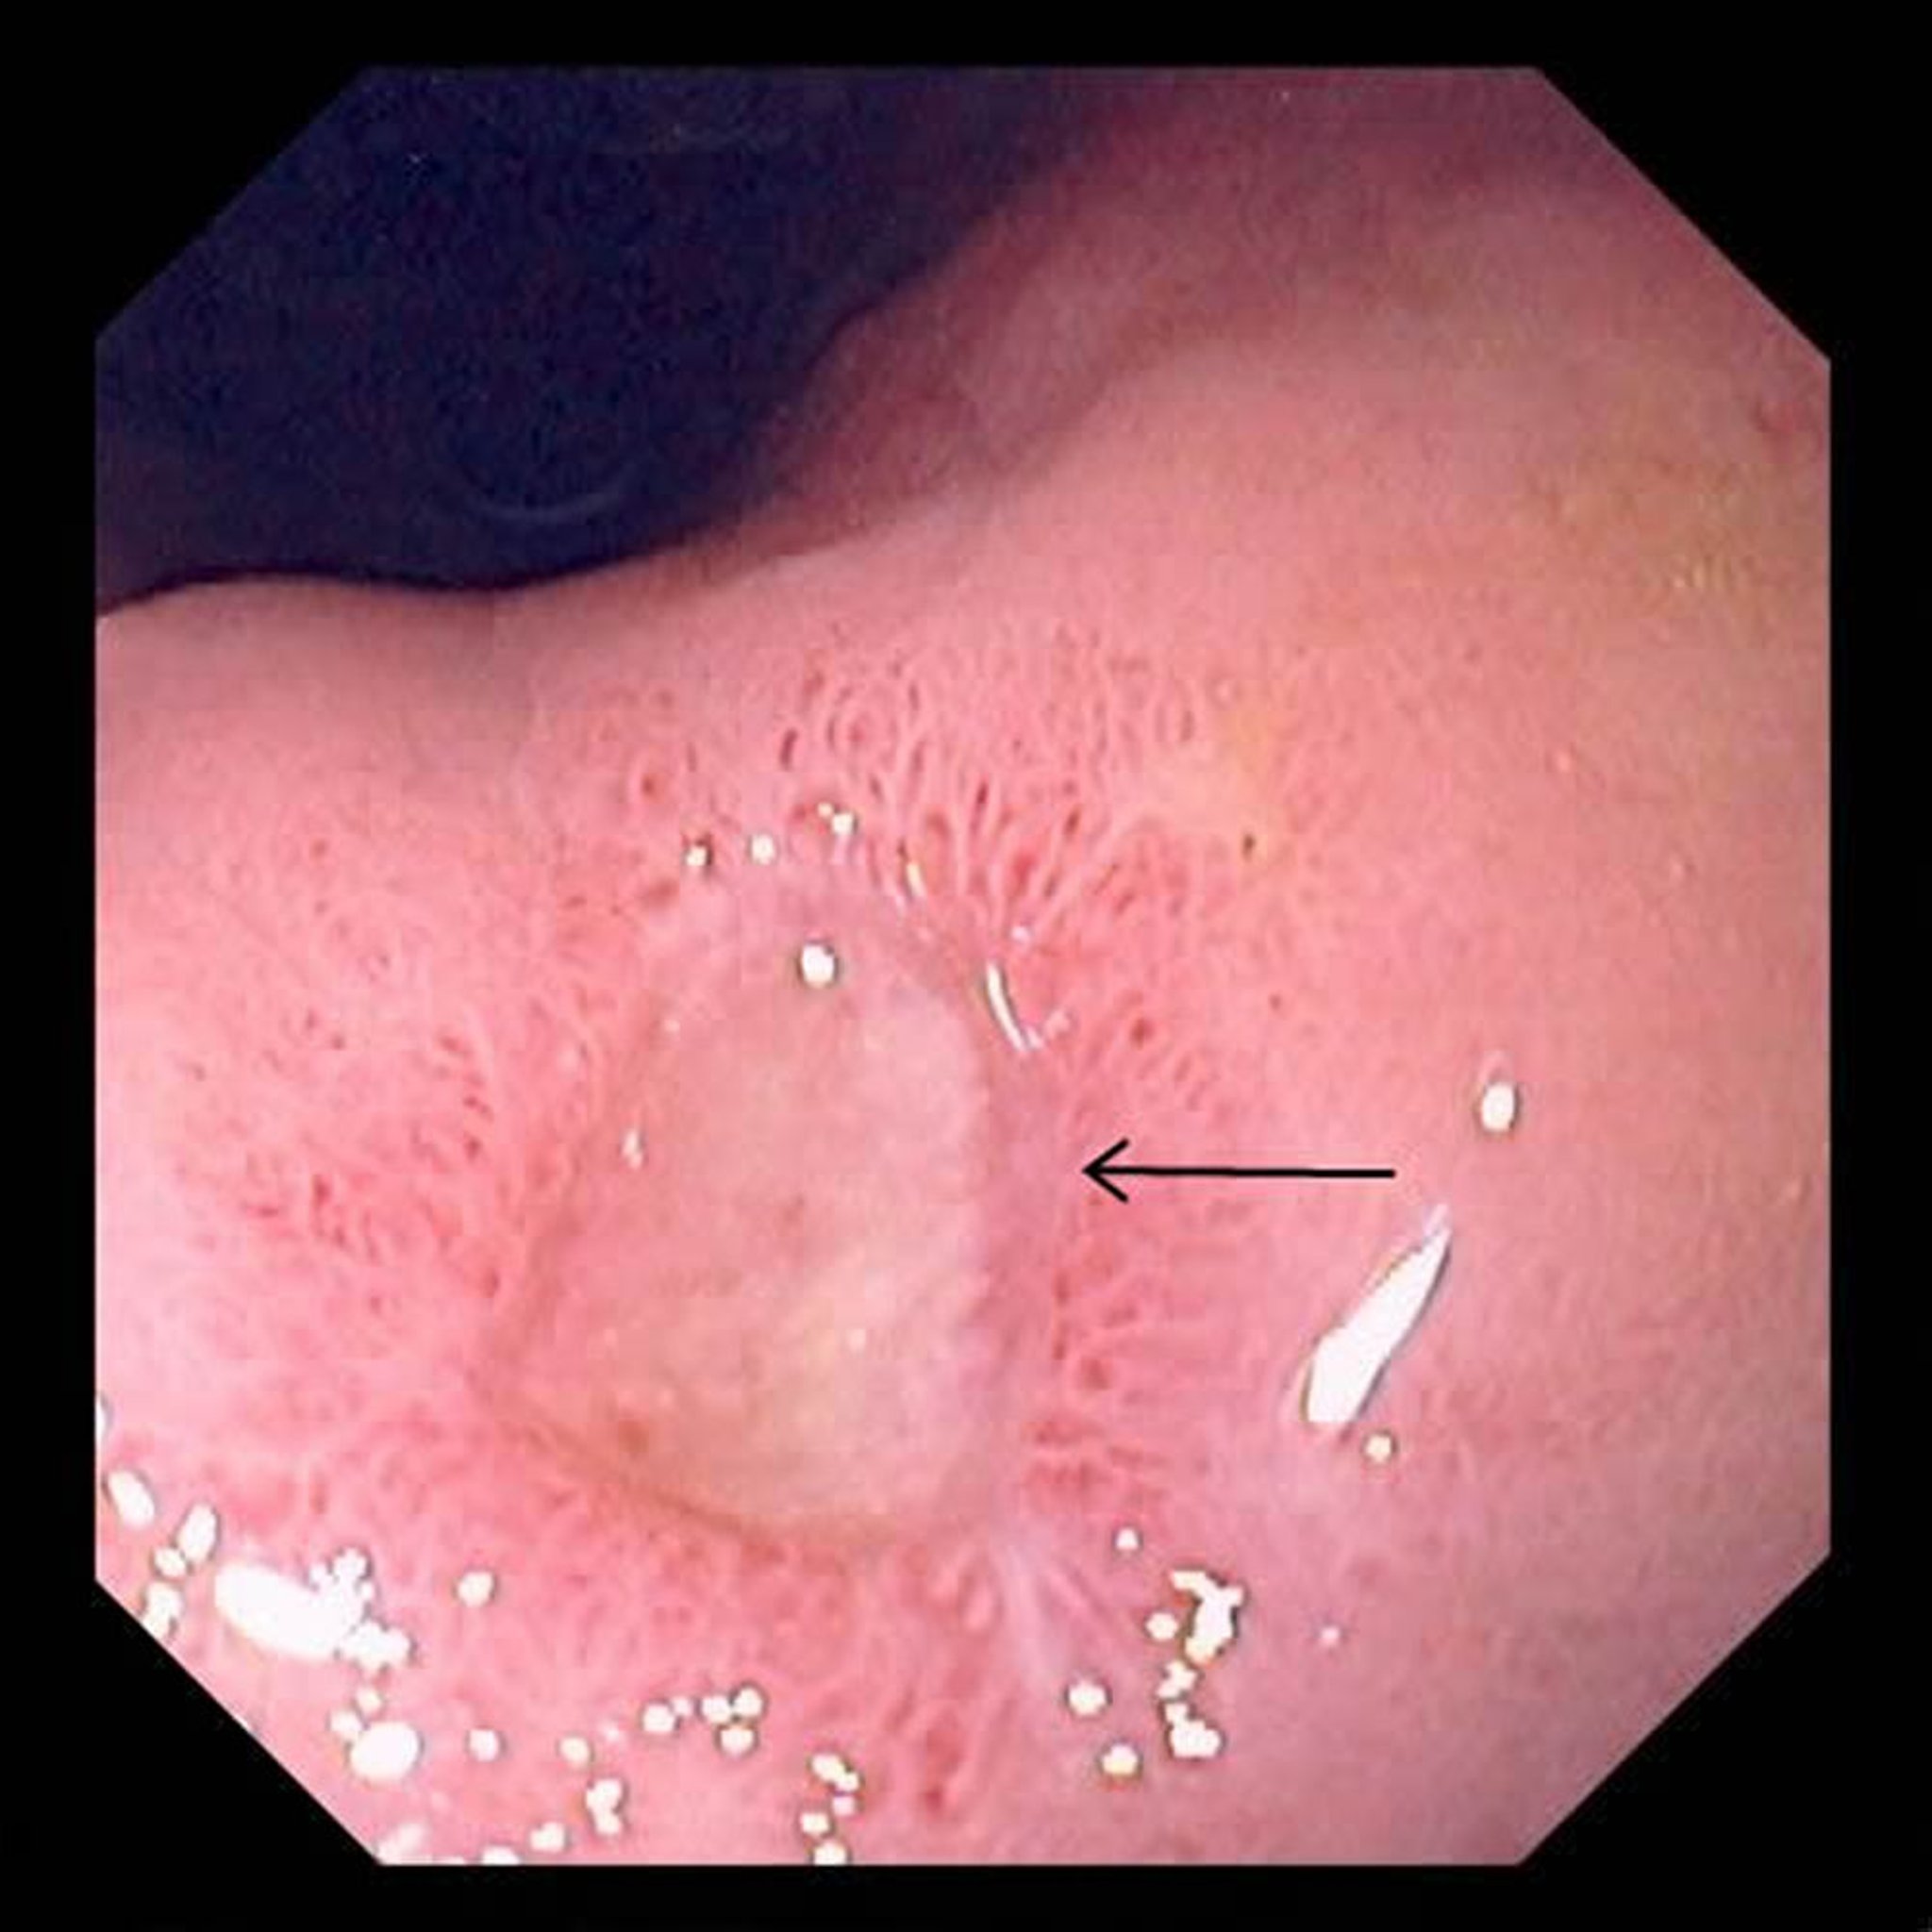

Ulcera gastrica

L’immagine mostra una grossa ulcera (freccia) nello stomaco.

Immagine fornita dal Dott. David M. Martin.